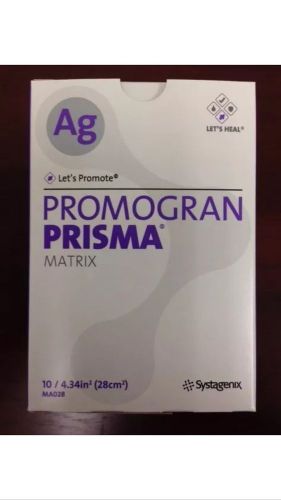

PROMOGRAN PRISMA AG MATRIX 4.34" 10/BX #MA028 SYSTAGENIX BOX: PLUS 2 EXTRA!!

PROMOGRAN PRISMA AG MATRIX 4.34" 10/BX #MA028 SYSTAGENIX: Expires 2/17